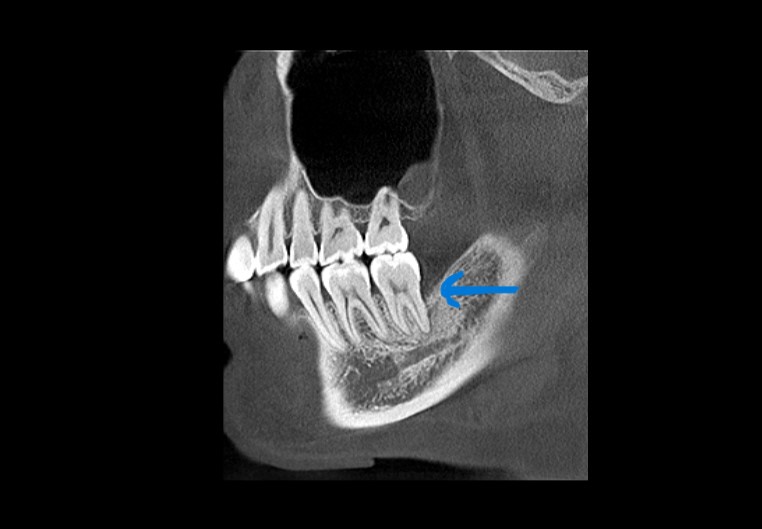

手術で歯ぐきを開き、徹底的に洗浄をし再生のための薬と人工骨を併用し、治療を行いました。

術後

レントゲン上で根っこの先端付近まで黒く抜けている部分が白くなっています。

骨が回復している様子が見られます。